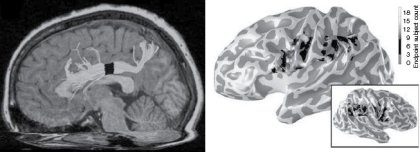

En el principio fue el número. Quizás antes que el cerebro. Luego juntaron sus caminos, convirtiendo nuestra capacidad de ver el mundo matemáticamente en un verdadero sentido —para algunos, el sexto sentido de nuestro cuerpo—. Ahora bien, ¿qué le pedimos a un sentido? Por ejemplo, que existan áreas cerebrales especializadas que se activen cuando desarrollamos esa experiencia sensorial. Eso es lo que ocurre, de hecho, con los números, tanto en cerebros de primates no humanos como en el nuestro; en efecto, allá por el área parietal (un poco más arriba que las orejas, ideal para el cabezazo certero y al ángulo), se producen respuestas a los estímulos de cantidades. Un verdadero mapa cerebral de los números y, por cierto, uno muy preciso: Stanislas Dehaene y su grupo demostraron que existen áreas parietales diferentes para la estimación o la comparación numérica, y otras, por ejemplo, para la multiplicación.

Desde que se escribió este libro, cerca de quince años atrás, un frenesí de investigación innovadora ha dado a esta área un ímpetu más fuerte que el que nunca imaginé. La cognición matemática es hoy un campo importante de la ciencia cognitiva, y ya no se centra exclusivamente en el concepto del número y sus orígenes, sino que se ha expandido a los campos relacionados del álgebra y la geometría. Varios temas de investigación que fueron apenas esbozados en este libro se han convertido en áreas de investigación por derecho propio: el sentido numérico en los animales, neuroimágenes de cómputos matemáticos, la naturaleza de la discalculia (el déficit en los niños que tienen dificultades matemáticas), etc. Uno de los logros más emocionantes ha sido el descubrimiento de neuronas independientes que codifican el número en el cerebro del mono, en una localización precisa en el lóbulo parietal, que parece ser un homólogo plausible de las regiones corticales que se activan cuando hacemos cálculos mentales. Otra corriente de investigaciones en constante y veloz desarrollo está relacionada con la aplicación de este conocimiento a la educación: ya empezamos a comprender cómo la escuela desarrolla un sentido exacto del número y la aritmética, y cómo se puede ayudar con juegos y programas informáticos pedagógicos muy simples a los niños que están en riesgo de desarrollar discalculia.